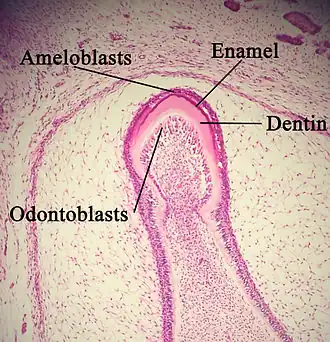

Enamel formation is part of the overall process of tooth development. Under a microscope, different cellular aggregations are identifiable within the tissues of a developing tooth, including structures known as the enamel organ, dental lamina, and dental papilla.[15] The generally recognized stages of tooth development are the bud stage, cap stage, bell stage, and crown, or calcification, stage. Enamel formation is first seen in the crown stage.

Amelogenesis, or enamel formation, occurs after the first establishment of dentin, via cells known as ameloblasts. Human enamel forms at a rate of around 4 μm per day, beginning at the future location of cusps, around the third or fourth month of pregnancy.[10] As in all human processes, the creation of enamel is complex, but can generally be divided into two stages.[3] The first stage, called the secretory stage, involves proteins and an organic matrix forming a partially mineralized enamel. The second stage, called the maturation stage, completes enamel mineralization.

In the secretory stage, ameloblasts are polarized columnar cells. In the rough endoplasmic reticulum of these cells, enamel proteins are released into the surrounding area and contribute to what is known as the enamel matrix, which is then partially mineralized by the enzyme alkaline phosphatase.[16] When this first layer is formed, the ameloblasts move away from the dentin, allowing for the development of Tomes' processes at the apical pole of the cell. Enamel formation continues around the adjoining ameloblasts, resulting in a walled area, or pit, that houses a Tomes' process, and also around the end of each Tomes' process, resulting in a deposition of enamel matrix inside of each pit.[3] The matrix within the pit will eventually become an enamel rod, and the walls will eventually become interrod enamel. The only distinguishing factor between the two is the orientation of the calcium phosphate crystallites.

In the maturation stage, the ameloblasts transport substances used in the formation of enamel. Histologically, the most notable aspect of this phase is that these cells become striated, or have a ruffled border.[16] These signs demonstrate that the ameloblasts have changed their function from production, as in the secretory stage, to transportation. Proteins used for the final mineralization process compose most of the transported material. The noteworthy proteins involved are amelogenins, ameloblastins, enamelins, and tuftelins. How these proteins are secreted into the enamel structure is still unknown; other proteins, such as the Wnt signaling components BCL9 and Pygopus, have been implicated in this process.[17] During this process, amelogenins and ameloblastins are removed after use, leaving enamelins and tuftelin in the enamel.[18] By the end of this stage, the enamel has completed its mineralization.